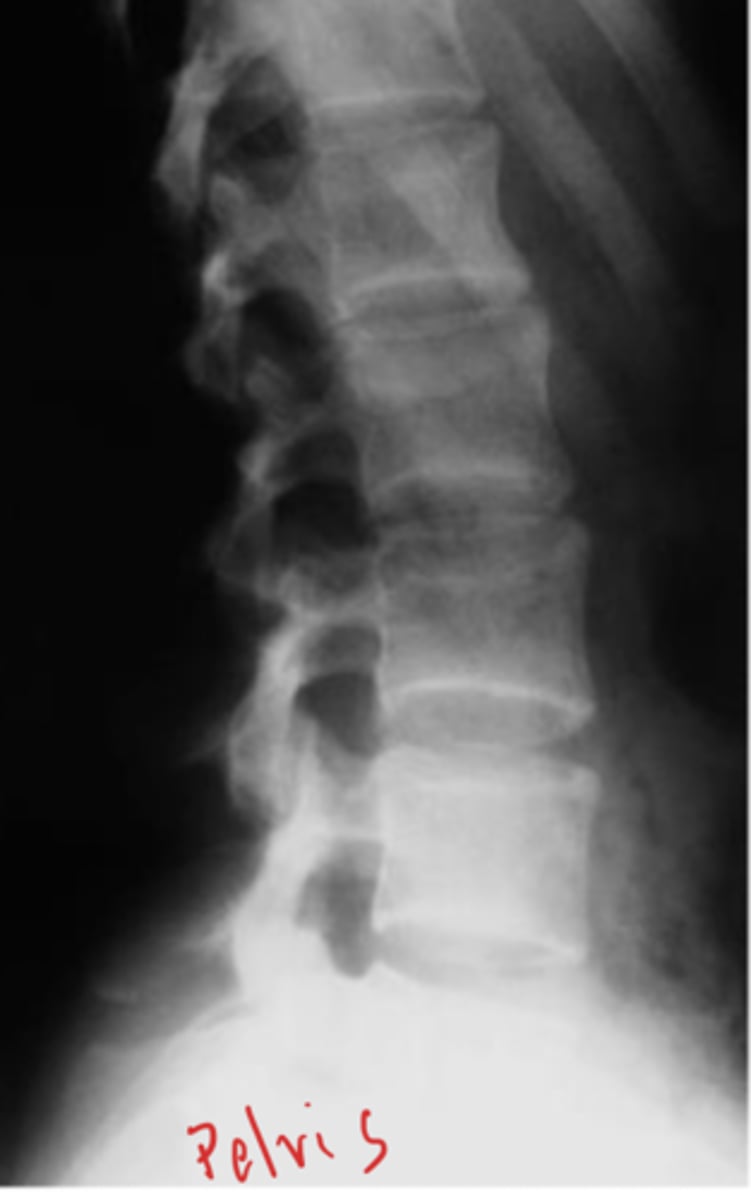

Lateral Lspine

What view is this?